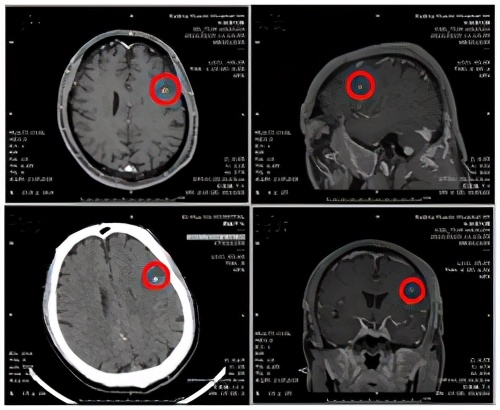

在随后的头颅核磁检查结果显示,患者左侧额叶有一大片异常信号,隐约可以看到中心有团块样东西,进一步完善头颅增强核磁检查,看到水肿带中间有一个环形强化结节,再结合头颅CT同一位置的高密度影,这些蛛丝马迹不禁让医生猜测:患者囊虫病治愈后已过去15年,真凶还可能是此病吗?或是脑肿瘤?右侧中脑亦见点状强化灶,是颅内多发转移瘤?

继续完善检查,患者经腰椎穿刺脑脊液压力升高,脑脊液常规、生化、细胞学均正常。外送血及脑脊液免疫系列、副肿瘤系列及囊虫、曼氏猎头蚴、肺吸虫抗体检查均阴性,被奉为感染性疾病“金标准”的二代测序检查,也未检出囊虫核酸。

为此,神经内科医师们进行激烈的疑难病例讨论后,一致认为,结合患者临床症状、影像学检查,高度怀疑为脑囊虫病,即使实验室检查结果未支持,也不能排除此诊断,临床仍考虑为脑囊虫病,建议进行驱虫治疗。